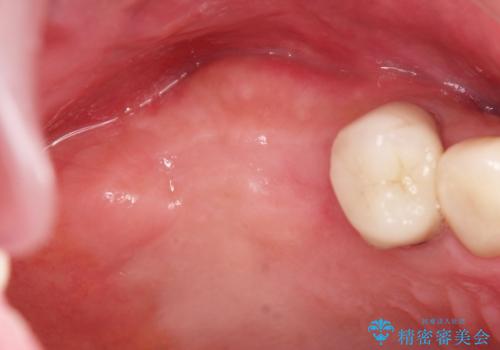

- 歯が抜けてしまい、噛めなくなった右側奥歯の治療を希望され来院されました。

しっかりと咬合機能の回復をするためにインプラント治療を選択されました。